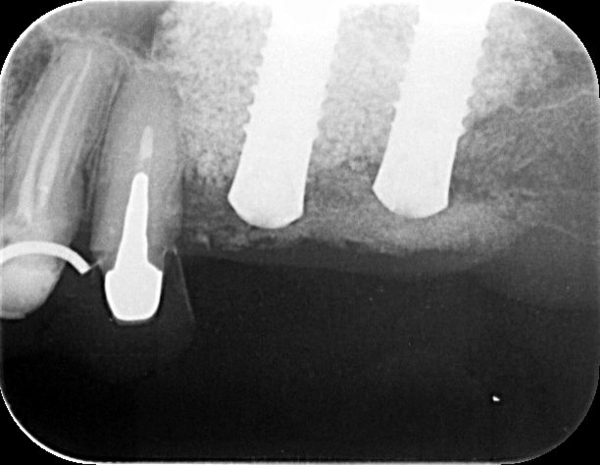

上の奥歯にインプラントを埋入する際に、骨の高さが足りなくて、サイナスリフトを併用しないとできない場合があります。その場合には、通常、先にサイナスリフトをして、6か月したらインプラントを埋入していきますが、

骨の高さが3mmあれば、サイナスリフトと同時にインプラント埋入をしていきます。

これで6か月の治療短縮ができます。

ストローマンの使用で、世界最短骨結合期間で定着します。